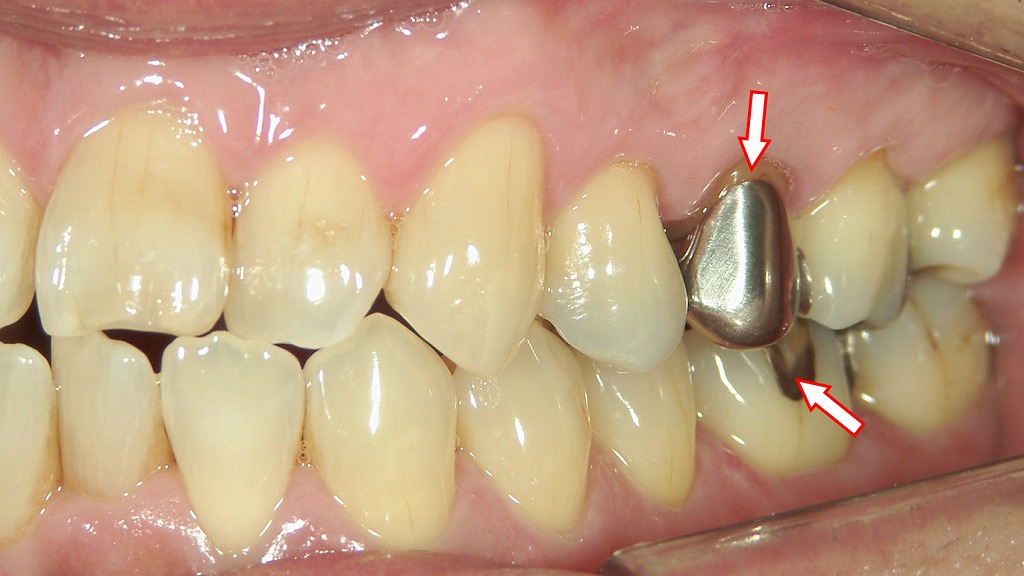

🪞保険の銀歯の見た目

この画像の赤い矢印で示された部分に 保険診療で装着された金属の補綴物(銀歯) です。

🦷 上顎第二小臼歯(赤矢印上)

- 銀色の**クラウン(全部被せ物)**が装着されています。

- これは一般的に「保険の銀歯(メタルクラウン)」と呼ばれるものです。

- 金銀パラジウム合金(いわゆる“銀歯”)が使用されており、強度は高いものの、

金属色が目立つため審美性(見た目)に劣るのが欠点です。

🦷 下顎第一大臼歯(赤矢印下)

- 銀色の部分的な詰め物(インレー)が見えます。

- こちらも保険の金銀パラジウム合金インレーで、虫歯治療後の欠損部を補うために装着されたものです。

- 咬合面のみに金属が見える形で、クラウンよりも削る量が少ないのが特徴です。

- 長期間使用すると、二次う蝕(再び虫歯ができる)や金属の腐食・変色が起こることがあります。

🔍 まとめ

| 部位 | 補綴物の種類 | 材質 | 特徴 |

|---|---|---|---|

| 上顎第二小臼歯 | 銀歯(クラウン) | 金銀パラジウム合金 | 強度は高いが審美性に劣る |

| 下顎第一大臼歯 | インレー(部分的な詰め物) | 金銀パラジウム合金 | 保険適用、耐久性あり、見た目は劣る |

このような銀歯は保険適用で安価に治療できる利点がありますが、

最近ではより自然な見た目のセラミック・ハイブリッドレジンに変更する患者さんも増えています。